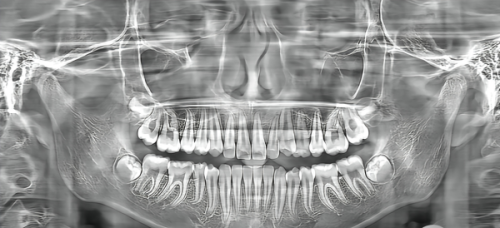

硬件设施:精品设备助力诊疗 门诊引进了海内外精品德国卡瓦3D全影CBCT和美国3Shape口内3D扫描及瑞士EMS舒适洁牙机等系统诊疗设备。这些高端设备不仅提高了诊断的正确率,也使得治疗过程更加舒适和效率高。